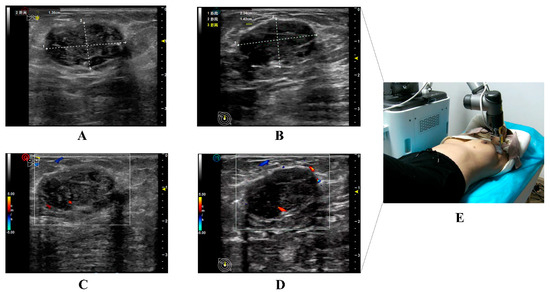

Figure 4. Illustration of the ultrasound images of the same target nodule in a 36-year-old woman obtained from conventional and 5G-based telerobotic ultrasound examinations. Grayscale US images of the same breast nodule from the (A) conventional US examination and (B) 5G-based telerobotic US examination. The US characteristics of the breast nodule are as follows: oval shape, parallel orientation, circumscribed margins, hypoechoic echo pattern, and posterior shadowing with no calcifications. The nodule is classified as BI-RADS 4. Colour Doppler flow images are from the (C) conventional US examination and (D) 5G-based telerobotic US examination. There are blood flow signals detected inside this breast nodule. (E) The transducer is located in the outer upper quadrant of the left breast. (US, ultrasound; 5G, fifth generation; BI-RADS, Breast Imaging Reporting and Data System).

In Scenario A, 34 breast nodules were detected using 5G-based telerobotic US and 35 using conventional US. Moreover, 32 breast nodules identified on 5G-based telerobotic US examination were consistent with those detected on conventional US examination (Figure 4). In addition to the breast nodules, two cases of gynecomastia, one of lactation mastitis, and one of postoperative breast effusion were diagnosed using both these US procedures.